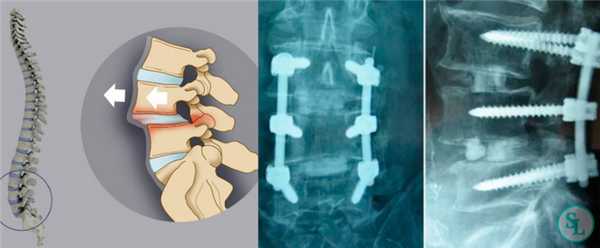

Чрескожная транспедикулярная фиксация - минимально-инвазивный метод оперативного вмешательства, при котором в педикулы позвонков через небольшие разрезы устанавливаются винты. Винты соединяются между собой стержнями. С помощью дополнительных приспособлений выполняется коррекция деформации. Данная методика обеспечивает стабильную фиксацию позвоночного сегмента на период срастания перелома или формирования спондилодеза.

Методика проведения операции:

Оперативное вмешательство осуществляется в условиях операционного блока под общей анестезией, в положении пациента на животе на рентген-прозрачном столе. Соблюдаются все асептические условия. После предварительной маркировки уровня повреждения под контролем ЭОП, в педикулы выше и ниже лежащих позвонков устанавливаются иглы Джамшиди G11. По иглам в позвонки вводятся спицы, производится разрез кожи и фасции, мышцы раздвигаются тубулярными дилятаторами. Канюлированными метчиками формируются каналы для винтов. По спицам в позвонки устанавливаются канюлированные транспедикулярные винты. В головки винтов заводится стержень, производится коррекция деформации ретракторами, стержни фиксируются гайками. Результат операции контролируется ЭОП-ом. Раны промываются антисептиком, послойно ушиваются. Накладывается асептическая повязка.

Транспедикулярная фиксация или ТПФ - операция, при которой позвонки фиксируются и стабилизируются при помощи специальных имплантов (транспедикулярных винтов). В каждом позвонке есть точка ввода винта, которую установил в 1985 году Рой Камилл — это точка пересечения поперечного отростка позвонка с верхнем суставным отростком. С помощью специальных инструментов в эту точку, вкручиваются винты определяя анатомически правильное расположение позвоночника, тем самым излечивая заболевание. Первые попытки установки имплантов были в 60-70 гг. прошлого века и с тех пор является «золотым стандартом» в лечения переломов и различных заболеваний позвоночника.

ТПФ выполняется под рентгеновским контролем, что позволяет хирургу точно контролировать каждое движение и избежать повреждения близкорасположенных анатомических структур. Чаще для этого используется ЭОП или КТ.

Очень важно при установки винтов соблюсти следующие моменты: отсутствие пространства между костью и винтом, исключение травматизации нервных и сосудистых структур или смежных дугоотросчатых суставов. Импланты устанавливаются согласно размерной линейки каждого позвонка и винта, бикортикально не касаясь замыкательных пластин.

Размер закрепляющих винтов для каждого больного подбирается индивидуально. Различают моноаксиальные и полиаксиальные винты, также разработаны варианты с боковой фиксацией стержня. Они вводятся по конвергентной монокортикальной методике, подразумевающей перфорацию позвонка только в точке входа винта.

Винты изготавливаются из титана, что гарантирует их высокую стойкость к различным деформирующим нагрузкам. Они оснащены поверхностными колпаками, обеспечивающими стабильность положения конструкции и ее защиту от перекоса. Все винты установленной системы объединяются специальными пружинистыми металлическими механизмами, что равномерно перераспределяет нагрузку на них.

Точка установки винта в корень дуги подбирается на основании расположения двух анатомических ориентиров - поперечного и суставного отростков позвонка. Непосредственно позвонок перфорируют с помощью специального зонда.